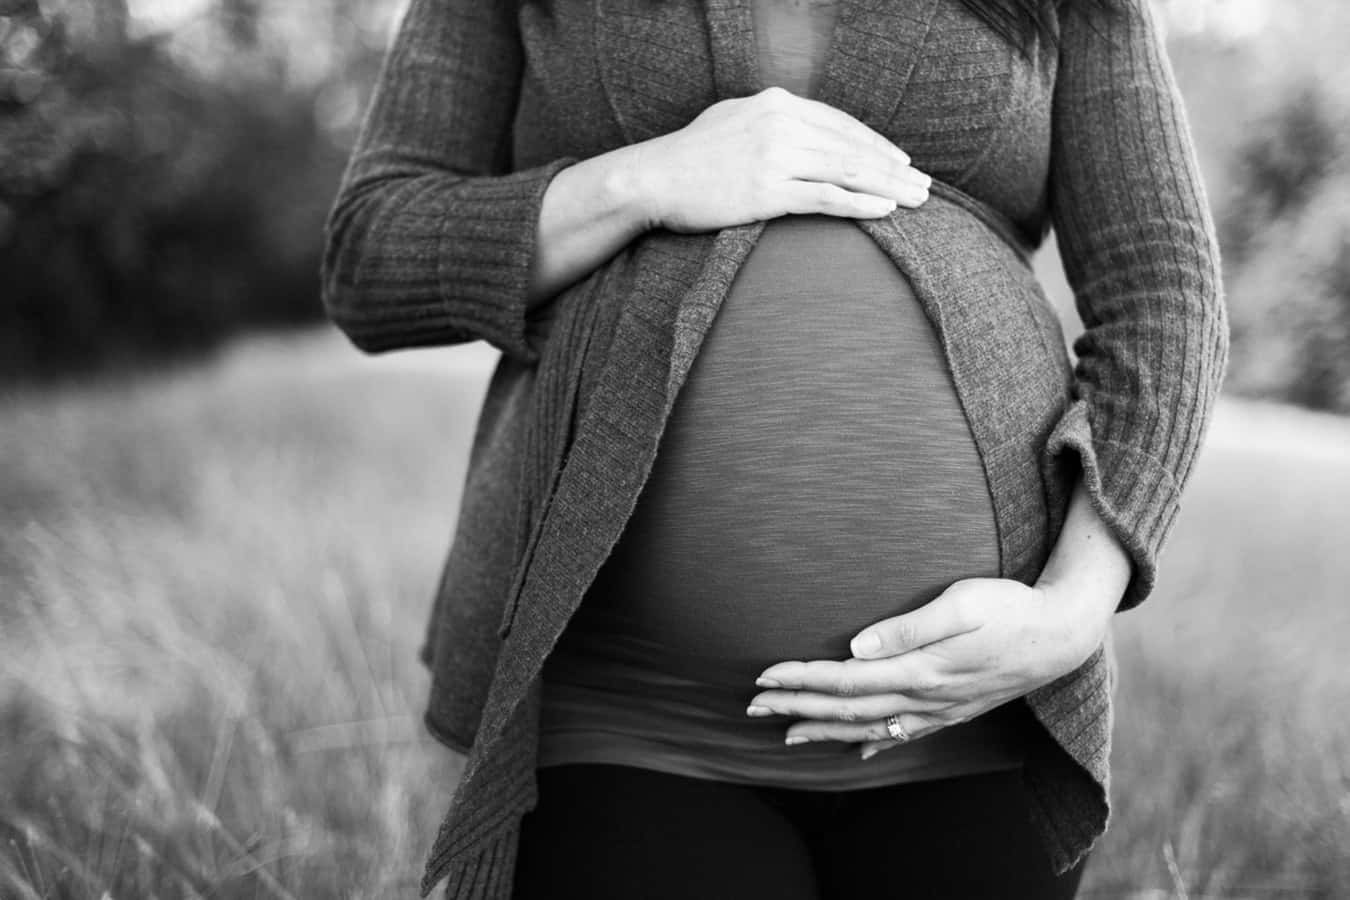

My neighbor was an ex emergency room nurse. Whenever we would ask her about strange cases, most answers were: “You don’t want to know.” The only story I have is really strange. One day, a morbidly obese woman rolled into the emergency room (her legs couldn’t support her weight anymore), and she complained about mild stomach pain.

After letting several people with mild ailments get treated before her, she sat up and rolled to the staff-only water cooler behind the counter. My neighbor told her about how the cooler was only for staff, and she started to go away. Midway, she stopped and from under her skirt, a baby fell on the floor. Apparently, this woman was pregnant and didn’t notice because of her weight. How the heck didn’t she feel giving the excruciating pain of giving birth?